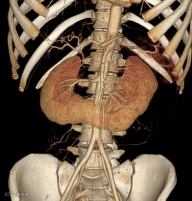

患者,男,60岁,因怀疑主动脉夹层而进行CTA检查,发现马蹄肾,肾峡部可见功能性肾实质,由三条肾动脉供血(箭头)。